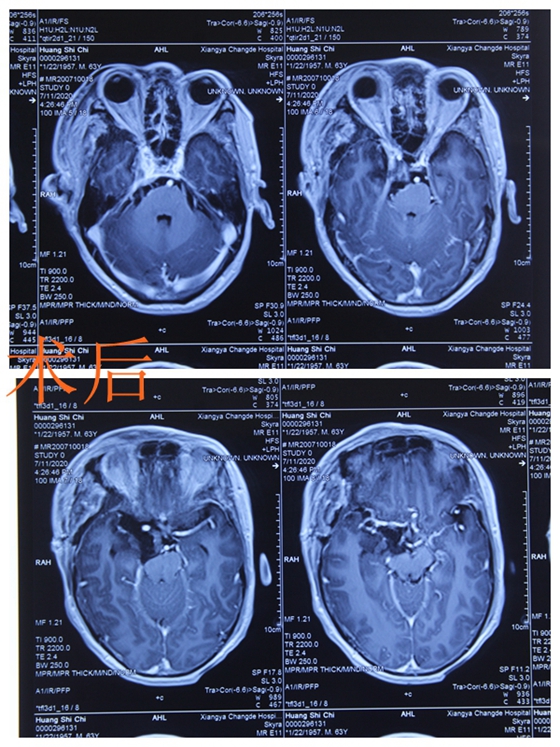

原来,在这3年间,黄先生视力下降的“罪魁祸首”竟是颅内长了一个鸭蛋大小的肿瘤。通过头部磁共振显示,右侧蝶骨嵴占位,且肿瘤有较大片钙化,占位已压迫到视神经,这才使得黄老先生的视力受到影响。当地医院告知家属需转往上级医院做进一步治疗,于是,家人带着黄先生慕名找到湘雅常德医院神经外科主任袁贤瑞教授就诊。

“黄先生的脑膜瘤位置较为特殊,位于右侧蝶骨棘内侧,向前延伸至视交叉前方,向后通过小脑幕裂孔压迫桥脑腹侧,向内压迫海绵窦,加上这个肿瘤生长已有几年时间,它与周围神经血管紧密黏连,手术中任何对患者神经或者血管的损伤,都会引起严重的后果。”袁贤瑞教授查看患者影像资料后表示,“需尽快进行手术。”

7月10日,由神经外科主任袁贤瑞主刀、主治医师张梨、侯小飞协助等组成的手术团队在显微镜下为患者实施开颅探查病灶切除术,经过8个多小时的紧张手术,袁贤瑞教授通过神经血管间隙将肿瘤完整切除下来。术中见肿瘤约5*4.5*4.5厘米大小,位于右侧蝶骨棘内侧,向额底包绕颈内动脉、后交通动脉、脉络膜前动脉、动眼神经并跨过右侧视神经进入第一间隙,侧裂下与侧裂静脉紧密黏连,并包绕大脑中及大脑前动脉起始部,海绵窦外侧壁受压。向后包绕大脑后动脉并穿过小脑幕切迹压迫桥脑腹侧,与基底动脉黏连不紧密。肿瘤质地较韧,有钙化,钙化主要位于天幕下脑干腹侧,与基底动脉、大脑后动脉关系密切。肿瘤血管丰富。术后患者恢复顺利,其视力、运动及语言功能完好。

术前

术后